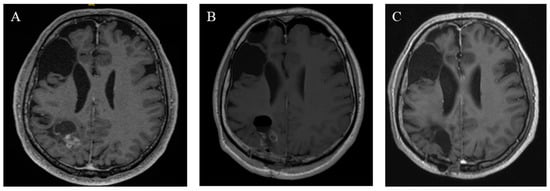

3.5. Follow-Up, Overall Survival, and Recurrence-Free Survival

Figure 5. Radiographic findings of case 11. (A) Preoperative T1 MRI with a contrast agent. (B) Postoperative MRI on the first postoperative day. (C) Three years of follow-up MRT after adjuvant radiation.